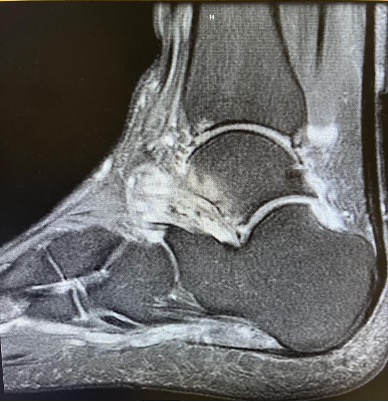

Physical examination showed pain with active and passive range of motion about the ankle most significant with inversion and dorsiflexion, as well as pain on palpation of the anterior medial ankle. Multiplanar, multisequence MR images of the right ankle without gadolinium contrast showed extensive marrow edema in the talus and sinus tarsi, as well as osteochondral cystic changes with bony irregularity involving the medial talar dome and focal cartilage defect to the anterior midline tibial plafond (see MRI images to left).